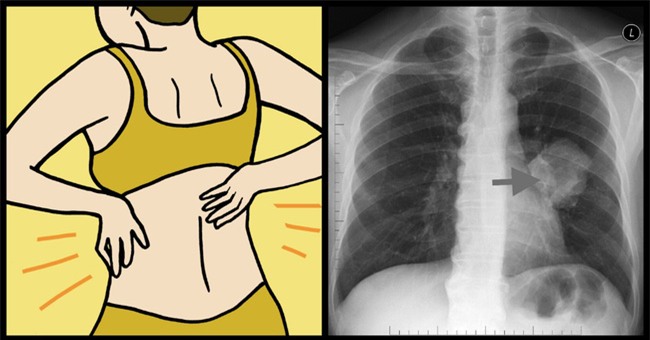

Cuối cùng, Rivas đã được chỉ định chụp X-quang và chẩn

đoán viêm phổi. Một vài tuần sau đó, cô đã rất mệt mỏi và bị sốt. Cô lại

tiếp tục đi khám và xét nghiệm thì thấy có một khối u ung thư đang phát

triển trên lá phổi bên phải. Cô đã được điều trị ngay thời gian đó.